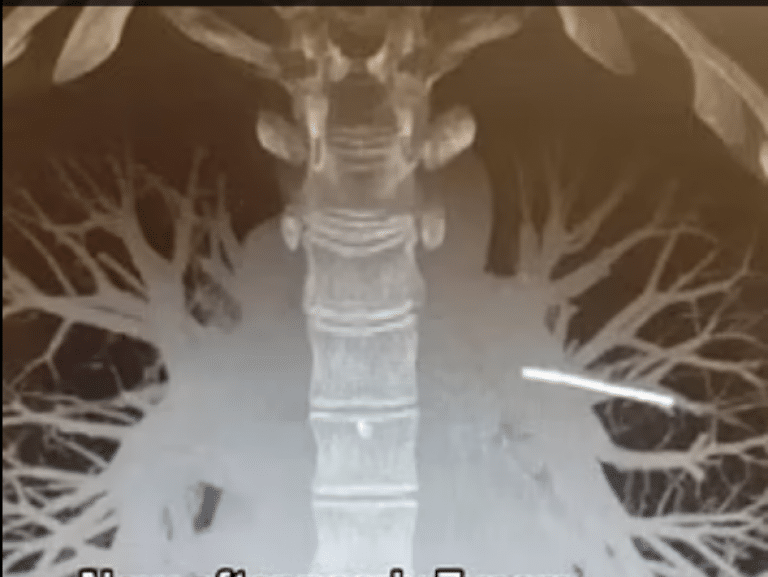

O femeie în vârstă de 29 de ani, mama a doi copii, a fost șocată să afle că dispozitivul său contraceptiv "dispărut" a ajuns în plămâni, iar medicii se tem că îndepărtarea acestuia ar putea provoca leziuni grave. Rebecca Hardy, în vârstă de 29 de ani, s-a prezentat la consultație pentru a-și scoate implantul